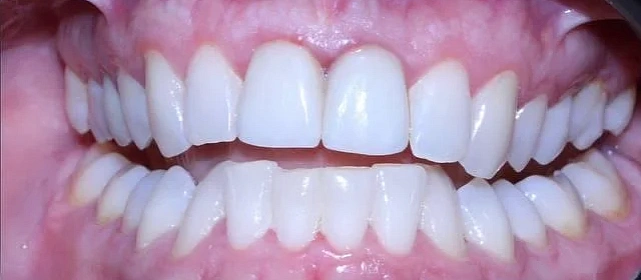

Результат

Зубы выровнены, скученность устранена, прикус исправлен, линия смыкания нормализована. Ретейнер установлен на нижнюю челюсть. На верхней ретейнер не ставили — на передних зубах коронки, вместо этого изготовлены ретенционные капы на обе челюсти. Пациентка направлена к ортопеду для замены коронок.

Решение: Поставили элайнеры Click на обе челюсти. Основной набор — 31 капа, плюс два дозаказа: 26 и 7 кап, итого 64. При этом лечение уложилось в 20 месяцев — быстро для такого объёма работы. Расширили дуги, убрали скученность, исправили прикус, выровняли линию смыкания. Ретейнер поставили только на нижнюю челюсть. На верхней от ретейнера отказались сознательно — на передних зубах коронки, и проволока там не ляжет корректно. Вместо этого изготовили ретенционные капы на обе челюсти. Ортопедию — замену старых коронок — пациентка будет проходить у себя в городе.

Непростой случай: II класс, сужение, скученность, деформация кривой Шпее и металлокерамические коронки на 11 и 21. Коронки ограничивают варианты ретенции — на верхней челюсти вместо ретейнера используем капы. Это осознанное решение, принятое совместно с пациенткой. 64 капы за 20 месяцев — хороший темп для такого объёма. Основной набор сделал базу, дозаказы довели до нормы.